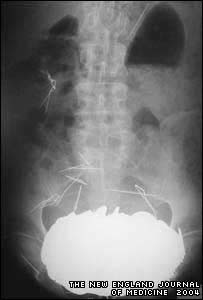

A equipe médica ficou espantada quando efetuou um raio-x e descobriu uma massa de 5,5kg, o equivalente a uma bola de boliche, no estômago do francês.

As moedas pesavam 5,5kg

As moedas e os outros objetos encontrados eram tão pesados que fizeram o seu estômago baixar até ficar à altura dos quadris.